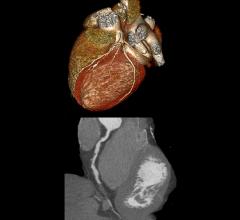

Feature | Dave Fornell

The key takeaway message from the Society of Cardiovascular Computed Tomography (SCCT) annual meeting in July was that…

The Society of Cardiovascular Computed Tomography (SCCT) annual meeting July 10-13 in San Diego covered the latest CT…